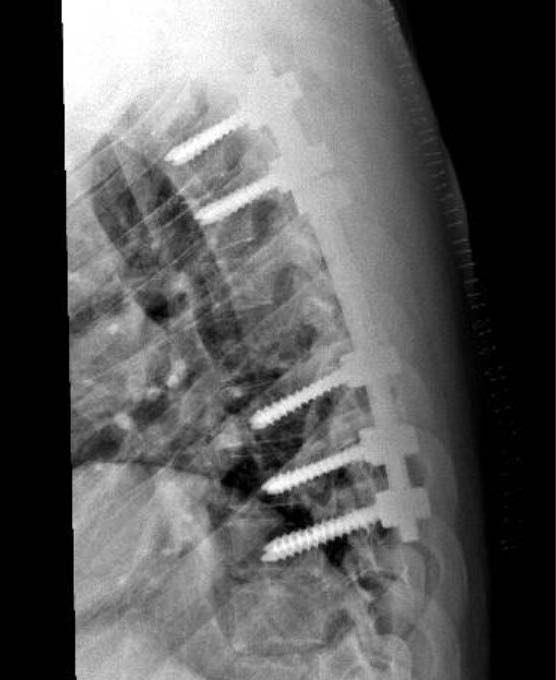

وأوضح استشاري جراحة العمود الفقري د.عبدالله حمد بأن الفحوصات الإشعاعية أظهرت وجود تآكل شديد في الفقرات الصدرية الخامسة والسادسة، وكذلك في الفقرة القطنية الخامسة، مع تآكل أقل شدة في الفقرة الصدرية الثانية عشرة، إضافة إلى الفقرتين القطنية الأولى والعجزية الأولى.

وبين د.حمد أن المريض كان مهددًا بالشلل، خاصة من مستوى الفقرة الصدرية السادسة، والقطنية الخامسة، وأن الفحوصات رجحت وجود درن (سل) بالفقرات.

وأضاف: أعطي المريض علاجًا لدرن الفقرات من أربعة أدوية، وأجريت له عملية تثبيت للفقرات الصدرية العليا، وتثبيت آخر للفقرات القطنية والعجزية، مع أخذ عينات من الفقرات المصابة للتشريح النسيجي، ولا يزال يتلقى العلاج وحالته في تحسن مستمر.